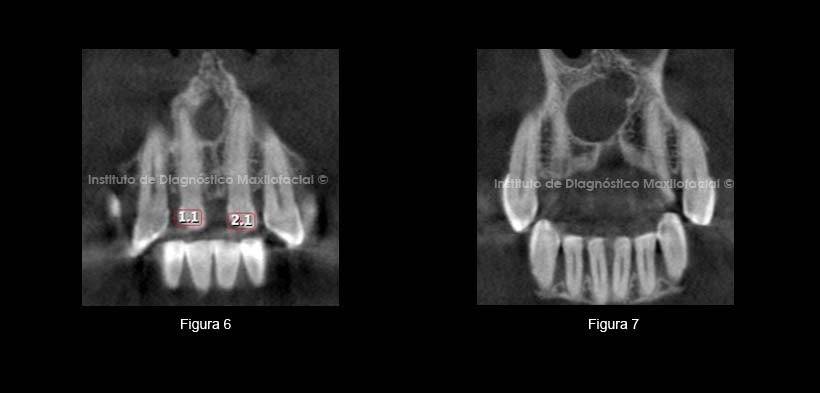

En cortes coronales apreciamos la extensión de la lesión. Un corte vestibular donde se aprecia parte de piezas 1.1 y 2.1 (Figura 6) y el segundo corte en zona palatina de la lesión donde se observa más amplia (Figura 7).